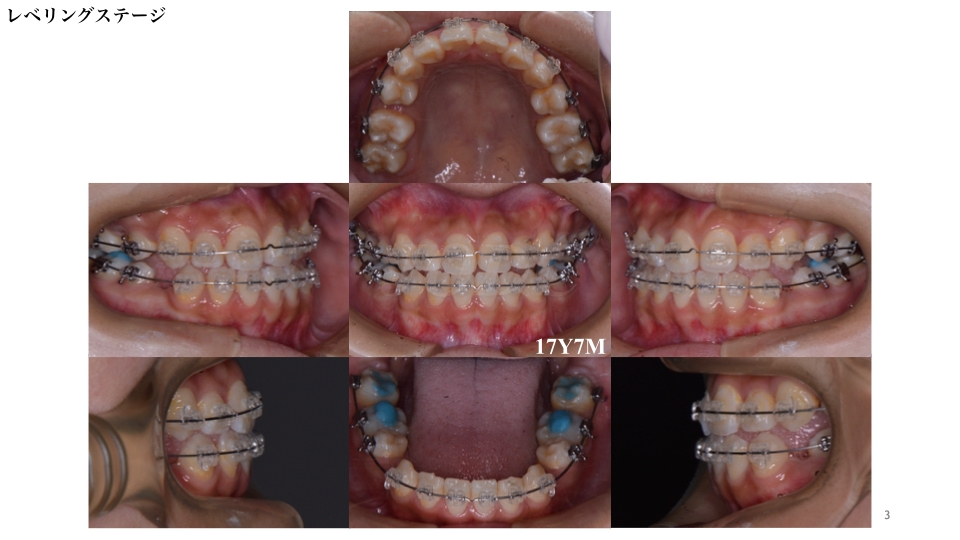

上下顎に装置をつけてから約3ヶ月後のレベリング(デコボコの改善)ステージです。